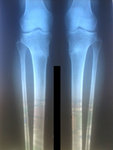

Ножки через 2 недели после снятия аппаратов!